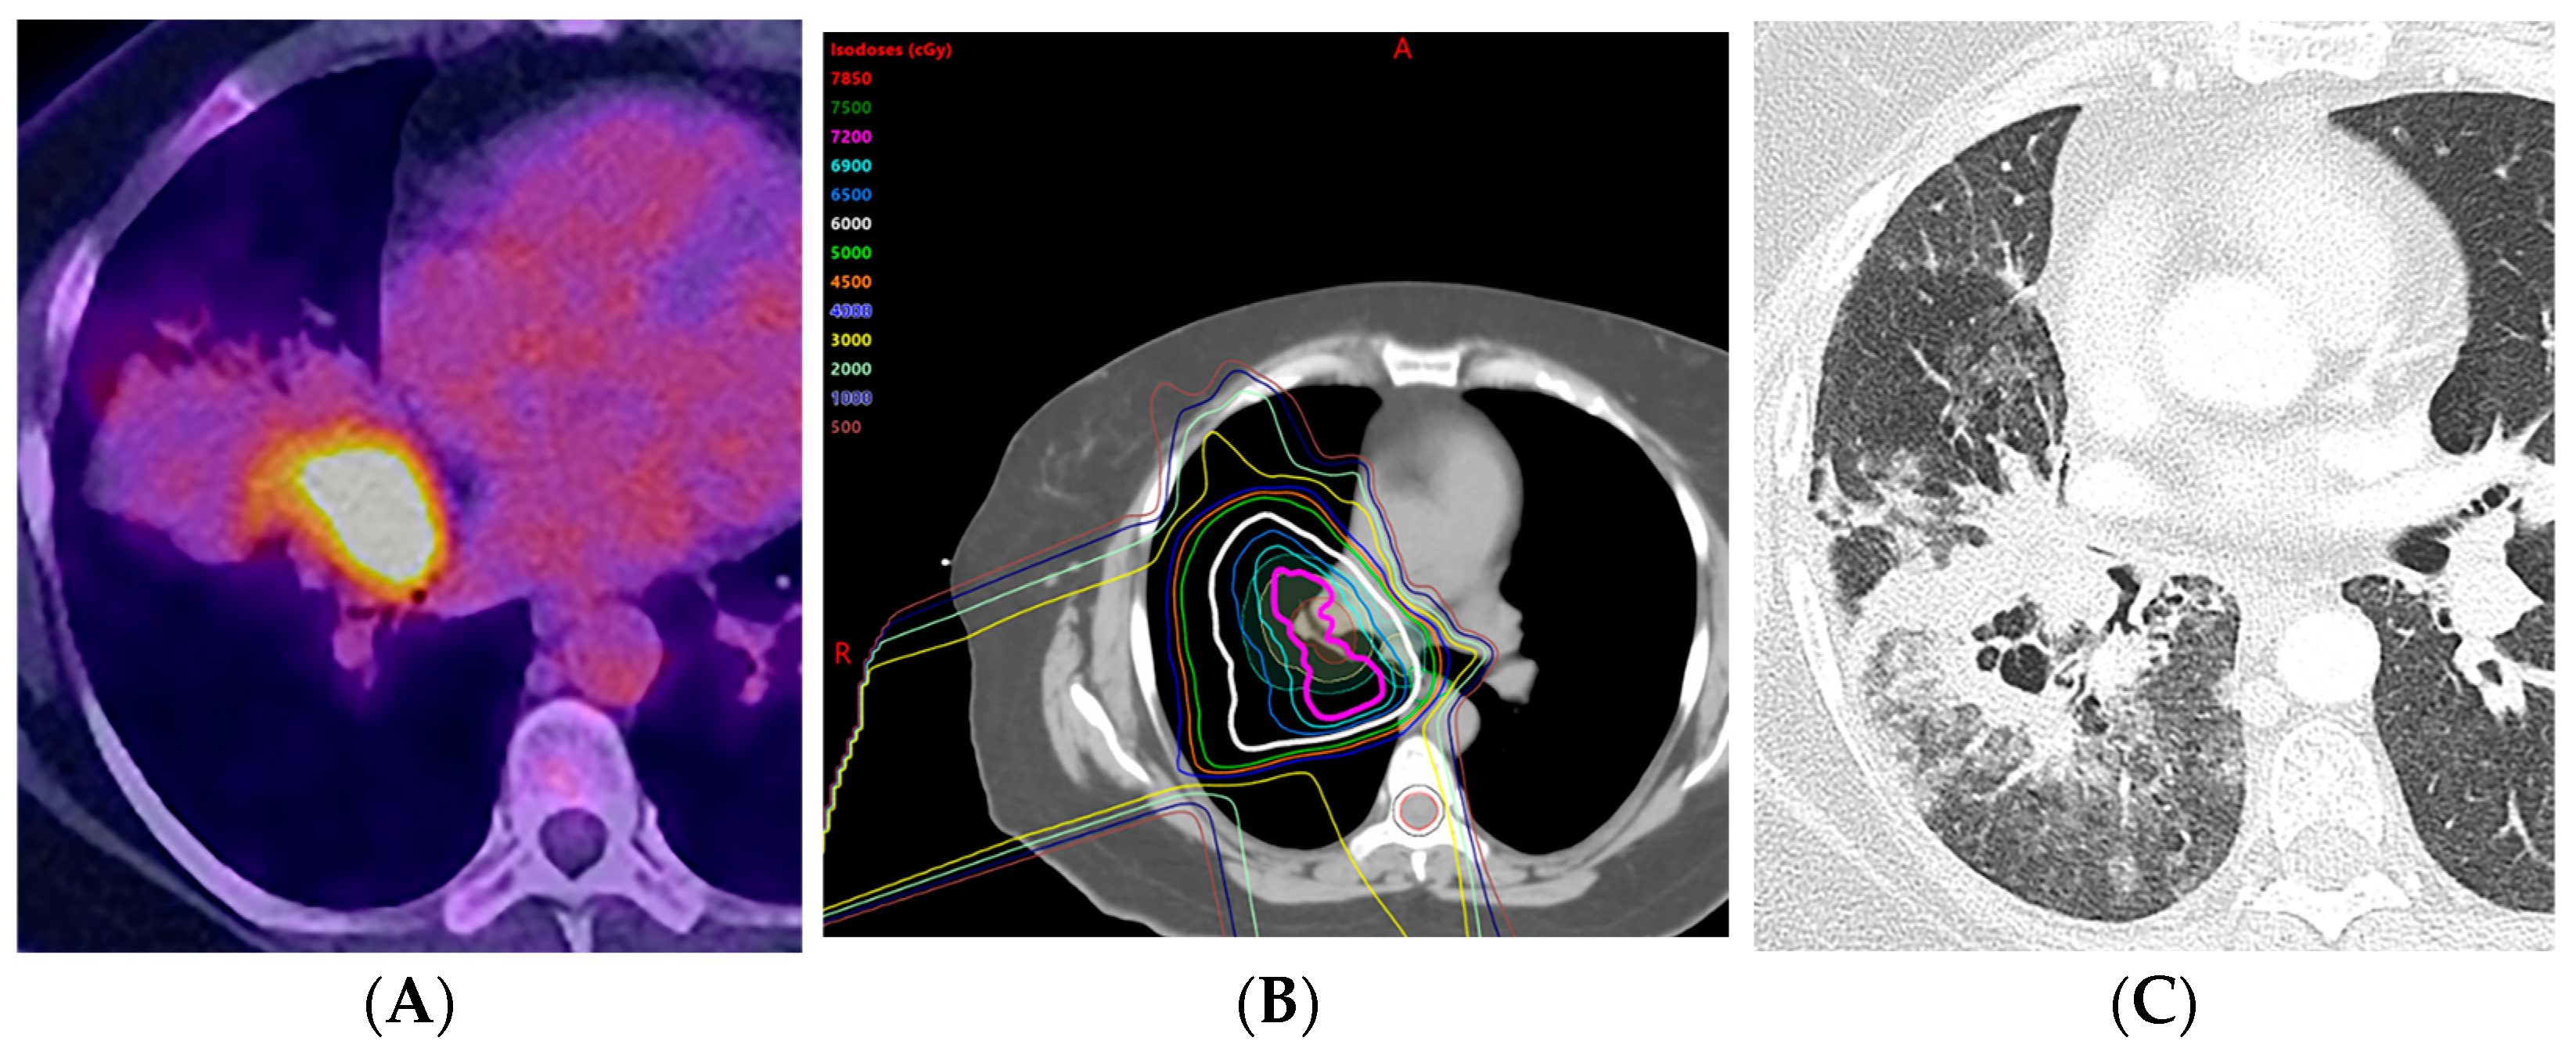

2.6. Proton Therapy